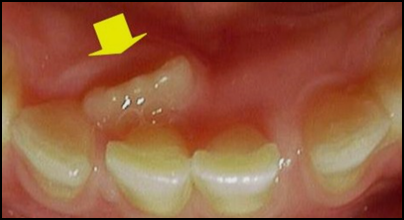

2. 이소 맹출

- 치아의 크기 등 여러가지 원인에 의해 치아가 비정상적인 위치로 자리 잡는 경우를 말합니다. 주로 큰 어금니, 아랫옆앞니, 윗송곳니에서 발생합니다.